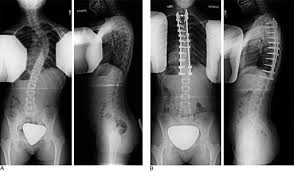

عند إجراء جراحة تصحيح العمود الفقري، يقوم الأطباء عادة باستخدام تقنيات مثل التثبيت الخلفي ودمج الفقرات لإعادة العمود الفقري إلى وضعه الطبيعي وتقليل زاوية الانحناء.

لكن في بعض الحالات، يظهر ما يُسمى بـ عدم توازن العمود الفقري، حيث يتكرر الانحناء أو يظهر انحناء جديد في مناطق أخرى من الظهر، سواء في الاتجاه الأمامي والخلفي أو على مستوى الفقرات القريبة من منطقة الدمج. هذا التكرار قد يؤثر على: